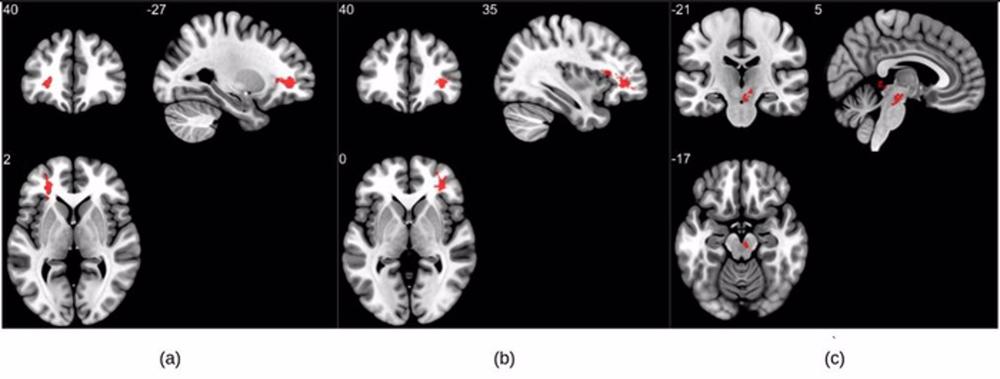

Los resultados de la resonancia magnética mostraron que los pacientes que se recuperaron de la COVID-19 tenían valores de susceptibilidad significativamente más altos en el lóbulo frontal y el tronco cerebral en comparación con los controles sanos. Los grupos obtenidos en el lóbulo frontal muestran principalmente diferencias en la materia blanca.

Las porciones de la circunvolución frontal orbital-inferior izquierda (una región clave para la comprensión y la producción del lenguaje) y la circunvolución frontal orbital-inferior derecha (asociada a varias funciones cognitivas, como la atención, la inhibición motora y la imaginería, así como a los procesos cognitivos sociales) y las zonas de materia blanca adyacentes conformaban los grupos del lóbulo frontal.

Los investigadores también encontraron una diferencia significativa en la región del diencéfalo ventral derecho del tronco cerebral. Esta región está asociada a muchas funciones corporales cruciales, como la coordinación con el sistema endocrino para liberar hormonas, la transmisión de señales sensoriales y motoras a la corteza cerebral y la regulación de los ritmos circadianos (el ciclo de sueño y vigilia).